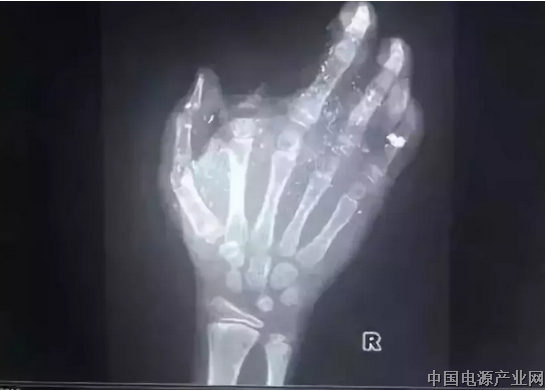

2018年1月,广西发生一起手机爆炸事件,一名年仅12岁的小男孩手掌被炸得血肉模糊,右手食指被炸没了,拇指、中指、无名指也都炸伤,失去了供血,手掌皮肤被炸得稀烂。